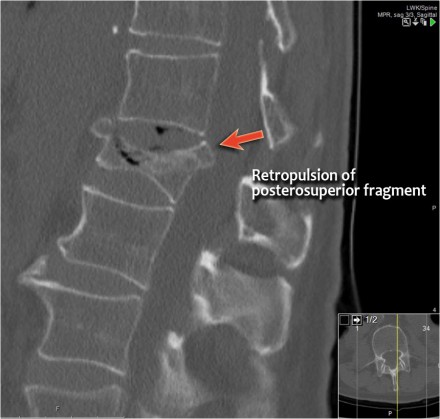

Retropulsion of posterosuperior vertebral body fragment

Retropulsion of a fragment is the typical feature of a burst fracture and distinguishes it clearly from a simple compression fracture.

- The morphology is of a vertebral fracture with retropulsion of a fragment, i.e. burst (2 points)

- The PLC is injured with edema of the interspinous ligament and a torn flaval ligament (3 points).

Based on imaging alone, the TLICS score is 5 points and this patient is a surgical candidate.